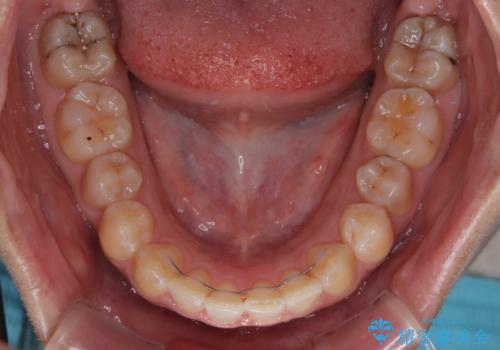

前歯のデコボコをインビザライン矯正で綺麗に改善

- 3年10ヶ月

気になる段差を納得いくまで改善させたため、治療期間は長くなりましたが、綺麗な仕上がりとなりました。